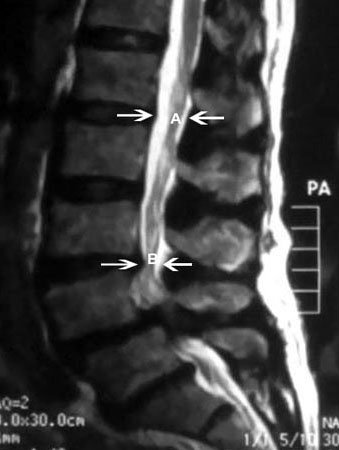

Ressonância nuclear magnética da estenose da coluna vertebral: (A) demarca o diâmetro sagital normal do canal vertebral. (B) demarca grave estenose do canal vertebral

Cortesia do Dr K. Singh; usado com permissão